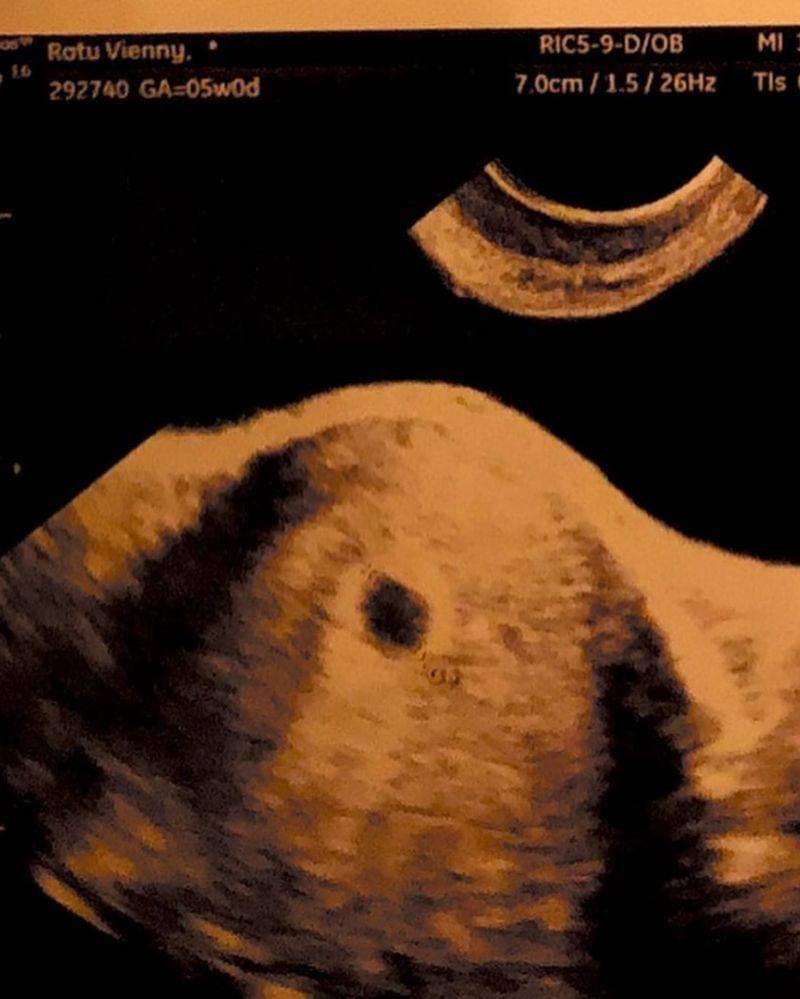

2. Potret USG calon buah hati Vienny

Masih dalam unggahan yang sama, Vienny juga menyertakan foto hasil USG bayi yang dikandungnya. Terlihat janin di dalam kandungan Vienny yang belum tampak jelas karena usia kehamilan yang masih muda.

Dalam unggahan tersebut, Vienny juga menuliskan sebuah caption yang singkat. "Little #16weeks," tulisnya.

Salah satu momen yang ditunggu-tunggu di masa kehamilan adalah saat periksa kandungan. Pasalnya, calon Mama bisa mengetahui perkembangan si Kecil dan melihat wajahnya dari layar USG.

Tak terkecuali dengan Vienny yang rutin mengunjungi dokter kandungan untuk mengetahui perkembangan calon bayinya. Lihat saja betapa gemasnya sang calon bayi Vienny yang tampak pada layar USG.